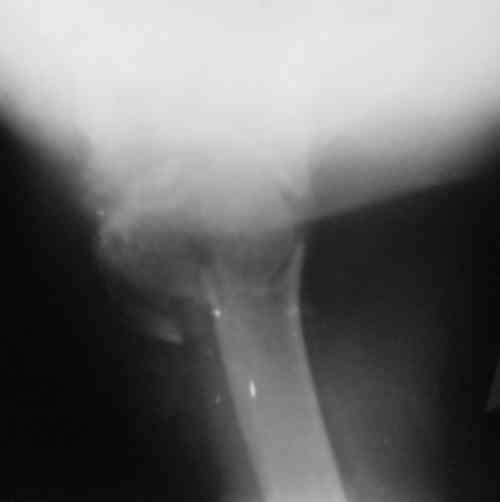

Судя по снимкам головка ротирована,успех закрытой репозиции, на мой взгляд, сомнителен, надо оперировать.

Судя по Р-граммам имеется оскольчатый перелом головки плеча. Во время открытой репозиции имеется большой риск "развалить" перелом, что значительно ухудшит кровоснабжения отломков. А так, на мой взгляд контакт м\у отломками достаточный, не смотря на наличие ротационного смещения головки думаю лучше продолжать консерватикное лечение. С уважением.

Судя по снимкам еще имеется перелом головки плеча, и чрезкостный отрыв вращательной манжеты. Для уточнения характера перелома не иешало бы сделать КТ. Если вести консервативно, то после сращения перелома будет ограничение движений в суставе не устраивающее больную. Я склоняюсь к оперативному лечению( накостный остеосинтез Т- Г образная пластина, лучше LCP для проксимальног плеча, обязательно подшить на место манжету).

В соответствии с работами Neer данный перелом можно классифицировать как однофрагментарный, так как нет диастаза более 1 см и углового смещения более 45 градусов - такие переломы лечатся консервативно. Рентген контроль каждые 10 дней- если смещение не увеличивается, то через 3-4 недели разработка движений в суставе

Уважаемый Сергей! Вы правильно написали критерии, но недооценили степень смещения в переломе хирургической шейки. Посмотрите ещё раз, это Two part fracture.

Снимки на 1-е сутки после репозиции и на 8- сутки после репозиции.